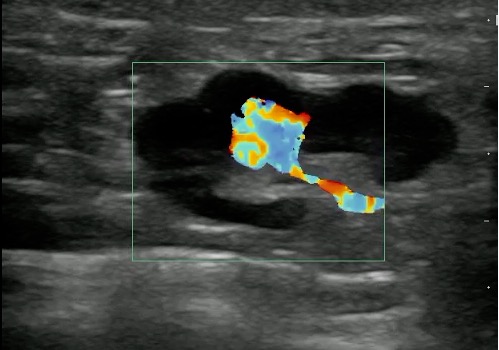

- Reactive lymphadenitis:

- Local infection or inflammation such as infections involving the pharynx, salivary glands, and scalp often cause reactive lymphadenitis.

- Normal reactive lymph nodes are enlarged, hypoechoic when compared with the surrounding structures. They still remain oval in shape.

- Vascularity is still confined to hilum of the lymph node and may be increased.

- Color Doppler of reactive lymphadenitis shows vascularity (normal along the hilum) which can differentiate from abscess cavity which has no flow within it.

Figure 13 and Video 10. Reactive lymph Node with increased Color Doppler